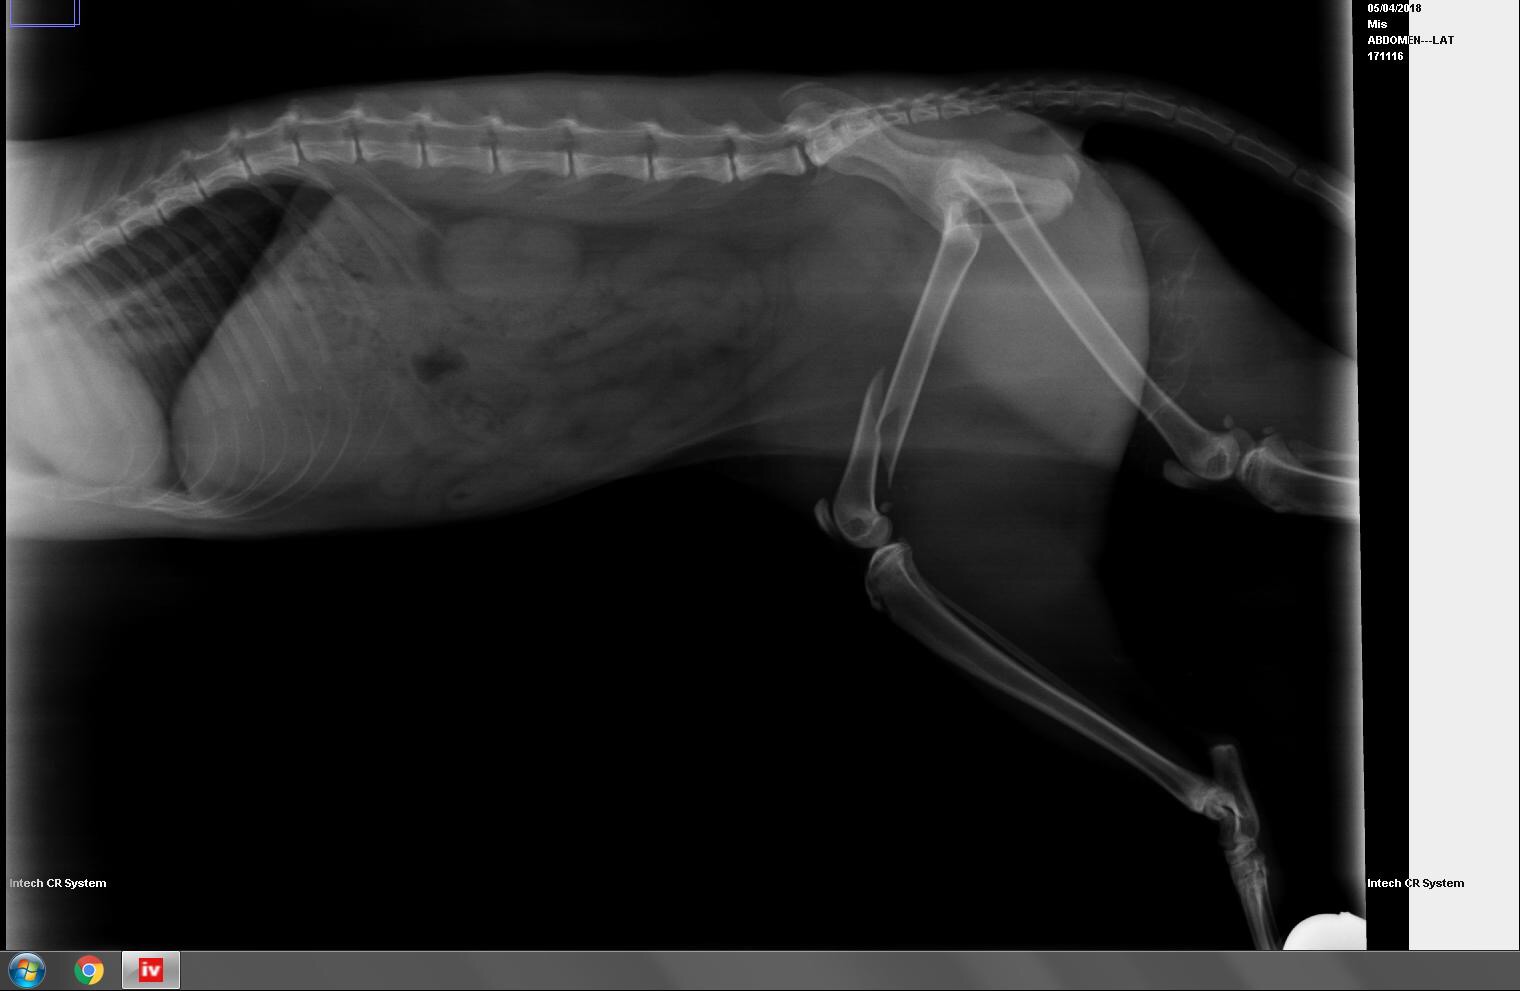

Una de las gatas de esta colonia fue atacada por un perro con el resultado de fractura de fémur. Sí, el bienestar de los gatos, en estas colonias, es posible, aunque ocurren accidentes como éste, que también se dan en un entorno casero.